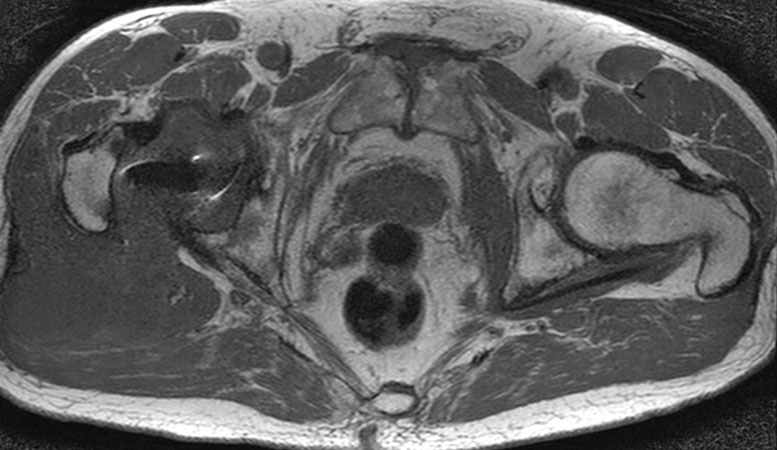

Hip imaging with metal implant using MARS at 1.5T

**Only for use with MR Safe or MR Conditional Implants by strictly following the Instructions for Use.